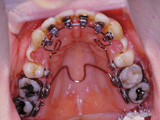

症例6:舌側矯正(見えない矯正治療)

治療前

治療途中

治療後